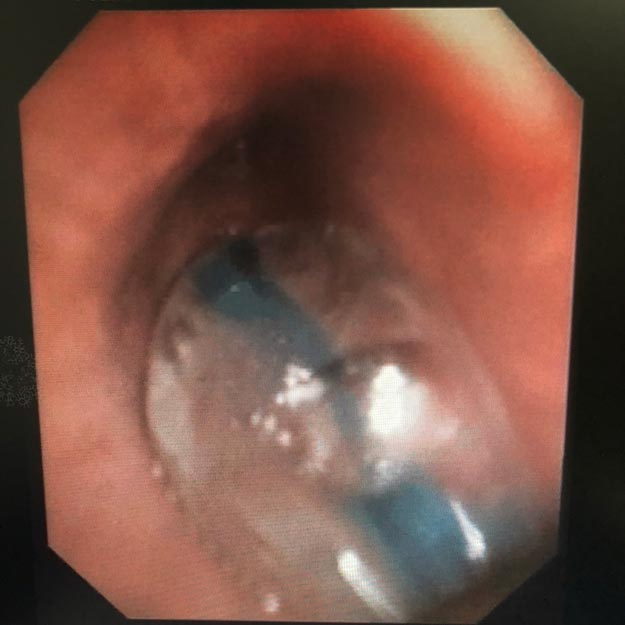

(陈阿姨增生的肉芽) 于是,呼吸内科医师决定再给陈阿姨做进一步的镜下治疗。在广州市第一人民医院呼吸科主任赵子文教授的指导下,市工人医院成功完成了第一例纤支镜球囊扩张术。经过规范的抗感染和纤支镜下介入治疗,陈阿姨最终康复出院。

(支气管球囊扩张术治疗中)